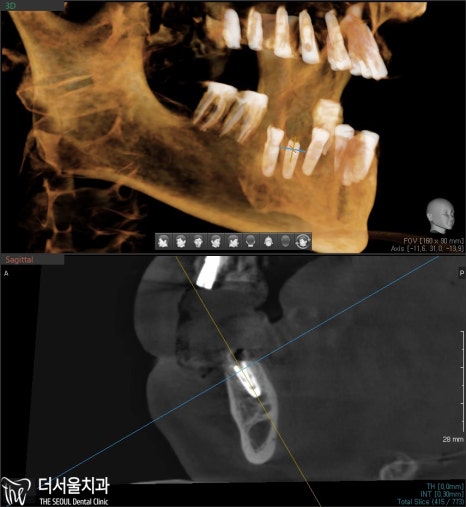

3. 정밀 분석

픽스처를 심기 전

수정구치과는 디지털 네비게이션을 이용하여,

각 위치에 맞는 임플란트 식립 계획을

모의 수술을 통해 꼼꼼하게 점검하고 세워봅니다.

이를 토대로 제작된 가이드를 이용해

픽스처를 빠르게 심을 수 있고,

최소 절개로 통증이 덜하며

빠른 회복이 가능합니다. ^^

다만, 여기서 알 수 있었던 사실은

16, 25, 26번의 잇몸뼈는 픽스처를 심기에

한참 모자란 상태였습니다.

그럼 보강해줘야 되겠죠?

상악동 거상술 후 생성된 공간 속에

뼈이식 재료를 옮겨드렸습니다.

그 다음, 만들어진 가이드에 맞춰

계획했던 위치에 픽스처를 꼼꼼하게 심어줍니다.

엑스레이 그리고 CT를 통해

한번 더 꼼꼼히 확인을 해서

잘 들어갔는지 봅니다.

계획했던 대로 잘 들어갔네요. ^^

식립하고 엑스레이와 CT를 찍어봤는데,

좋은 결과가 나왔네요. ^^